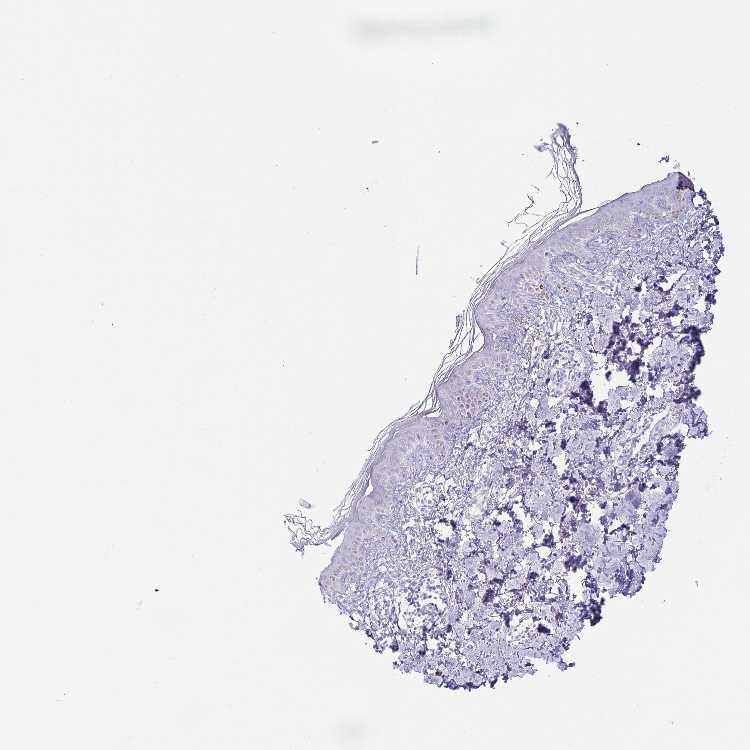

SKIN 1 - Antibody stainingi

Antibody staining in the annotated cell types in the current human tissue is reported as not detected, low, medium, or high, based on conventional immunohistochemistry profiling in selected tissues. This score is based on the combination of the staining intensity and fraction of stained cells.

Each image is clickable and will lead to virtual microscopy that enables deeper exploration of all samples and also displays staining intensity scores, fraction scores and subcellular localization as well as patient and tissue information for each sample.

Antibody HPA038224

Langerhans Not detected

Fibroblasts Not detected

Keratinocytes Not detected

Melanocytes Not detected